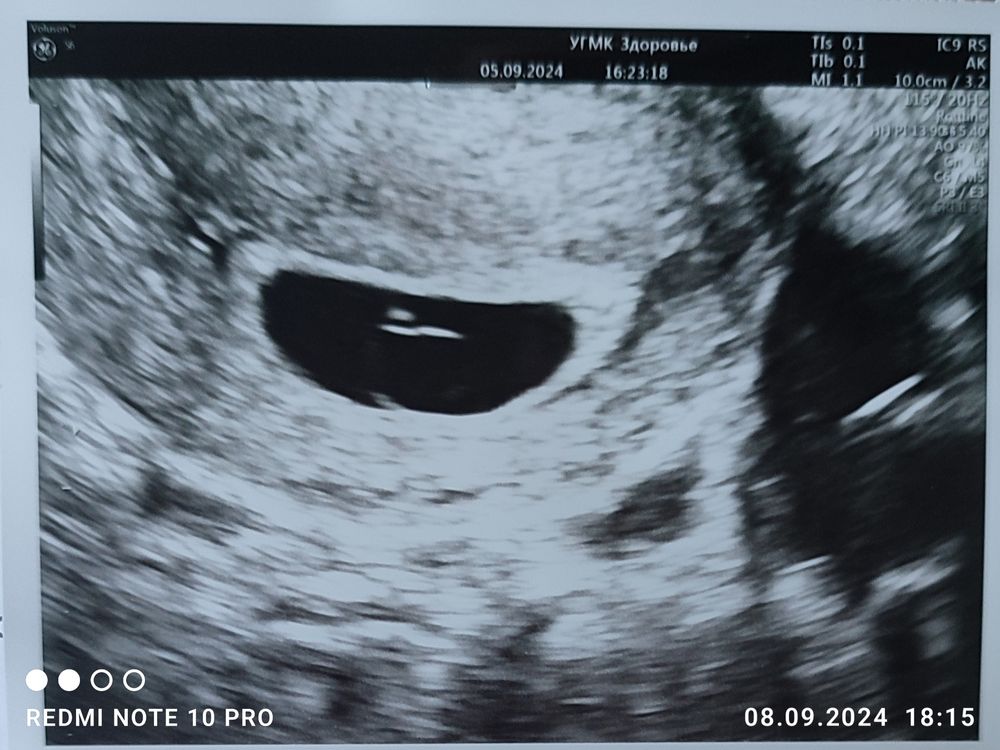

Марина, а вот это УЗИ делали при поступлении на стационар. Если честно, то я в принципе не понимаю, почему они посчитали, что их там двое. У нас в семье и предпосылок к двойне то и нет ни у кого, но пишу, как сказал врач. Завтра пойду на еще одно УЗИ. Изображение

Регина, в этом пя у вас как-будто два эмбриона,но плодное яйцо одно,если одно плодное яйцо на двоих,то хгч не должен падать,так как хгч вырабатывает оболочка плодного яйца,это когда два плодных,одно перестает развиваться,а второе растет, возможно хгч и может снижаться,а с одним пя не должно,короче все странно,надо мнение третьего экспертного УЗИ,а по месячным какой срок у вас ?